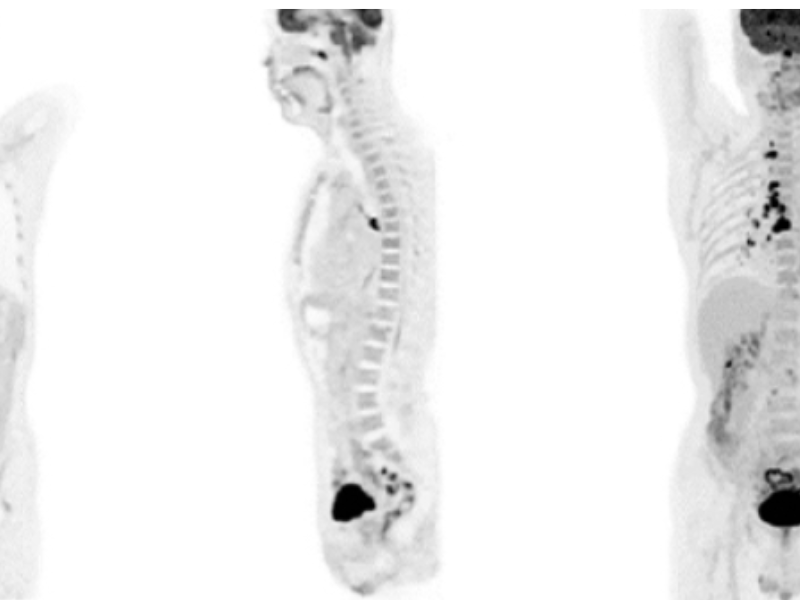

Clinical Application

Quantitative Accuracy for PET

High-Resolution PET

Lesion Detectability for PET

The Long axial 24 cm FOV and high system sensitivity enables whole-body scanning in 4 bed position within 8 minutes